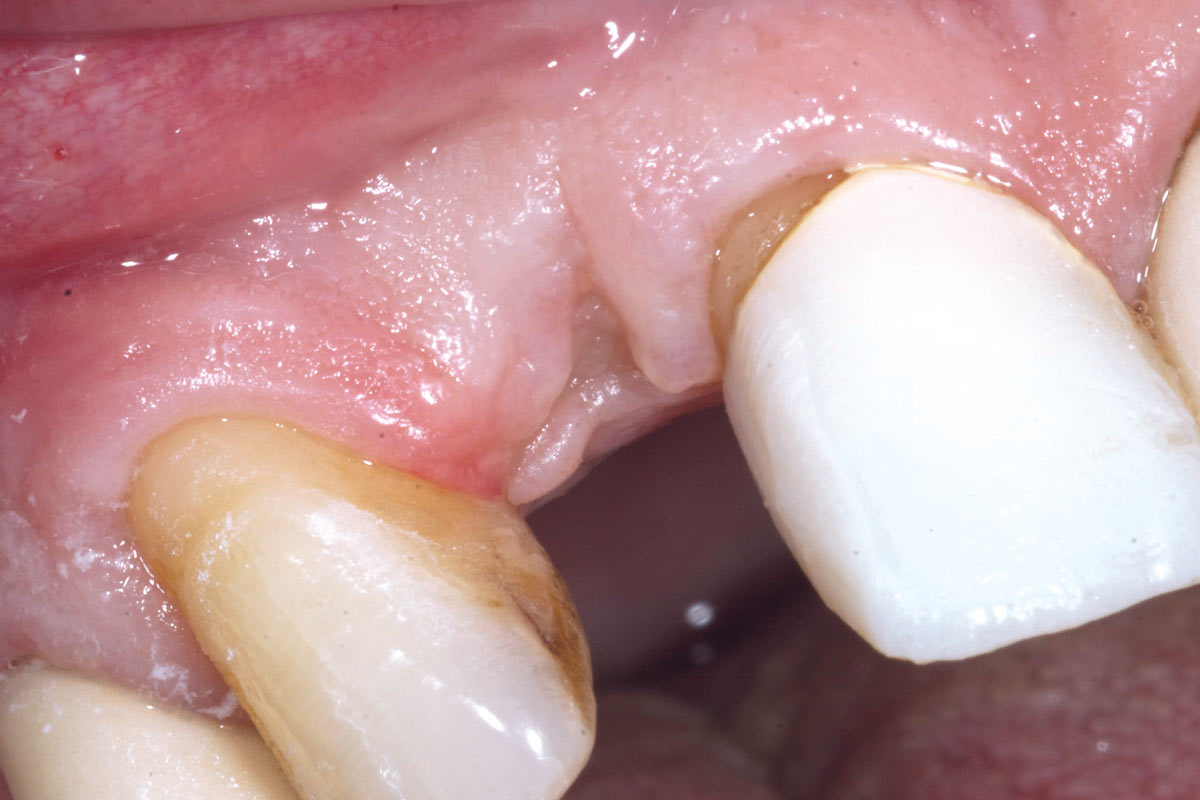

5/19 - 7 weeks after extraction of healing with a temporary tooth supported cantilever bridgeBone augementation with maxresorb® - Dr. R. Cutts

6/19 - Site without prosthetics showing sever buccal bone lossBone augementation with maxresorb® - Dr. R. Cutts